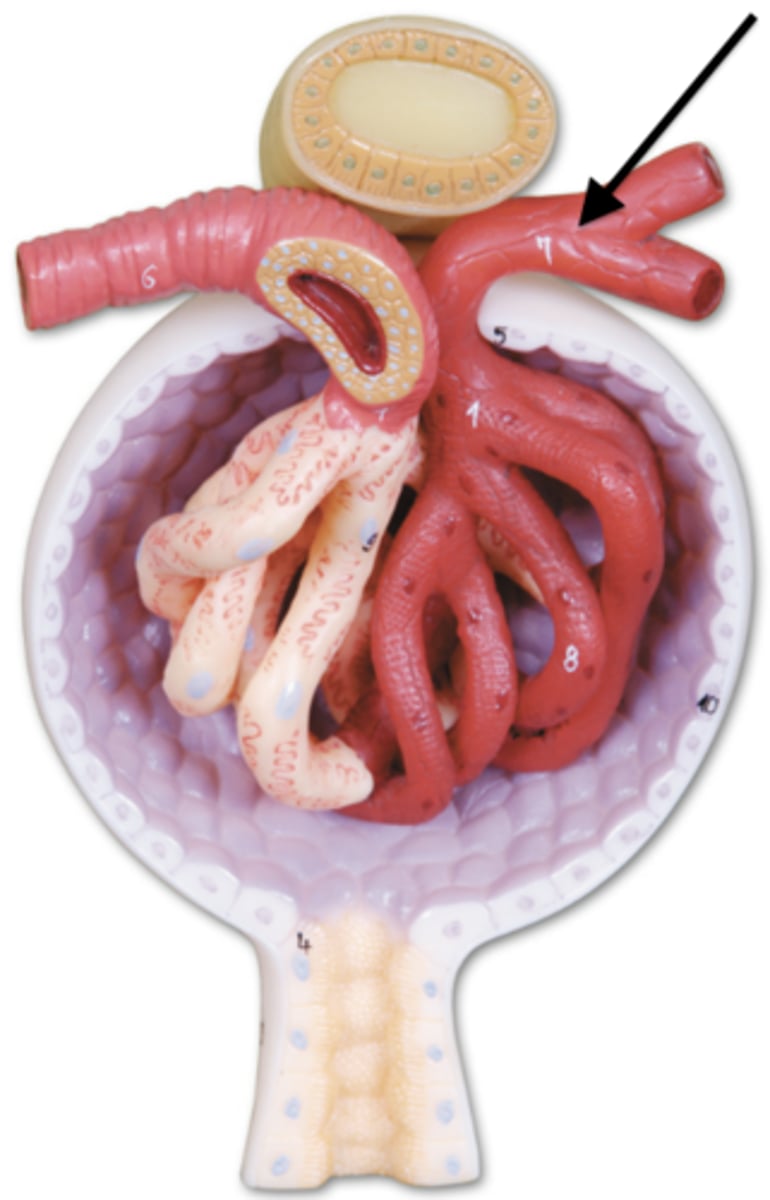

arrow

renal artery

renal vein

segmental

both vessels

interlobar

both vessels

interlobular

both vessels

arcuate

both vessels

afferent arteriole

efferent arteriole

glomerulus

juxtaglomerular apparatus

Bowman's capsule / glomerular capsule